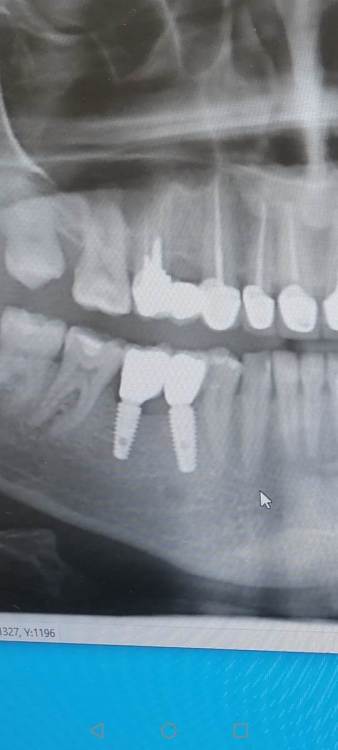

На снимке оголилось 2 витка резьбы

Добрый день уважаемые доктора. После установки коронок на импланты, беспокоит что на контрольном снимке оголилось 2 витка резьбы импланта.

Сами импланты установлены в ноябре.  Коронки на них поставили месяц  назад, закрутили с усилием 25 ньютонов, и поставили временную пломбу . Отправили на месяц гулять. Сегодня сделал снимок, пришёл к врачу врач сказала что все отлично. Докрутила на 35 и поставила постоянную пломбу. Но меня беспокоит что ушло несколько витков резьбы, хотелось бы услышать ваше мнение, скажите это нормально? По ощущениям ничего не беспокоит, жую без проблем.